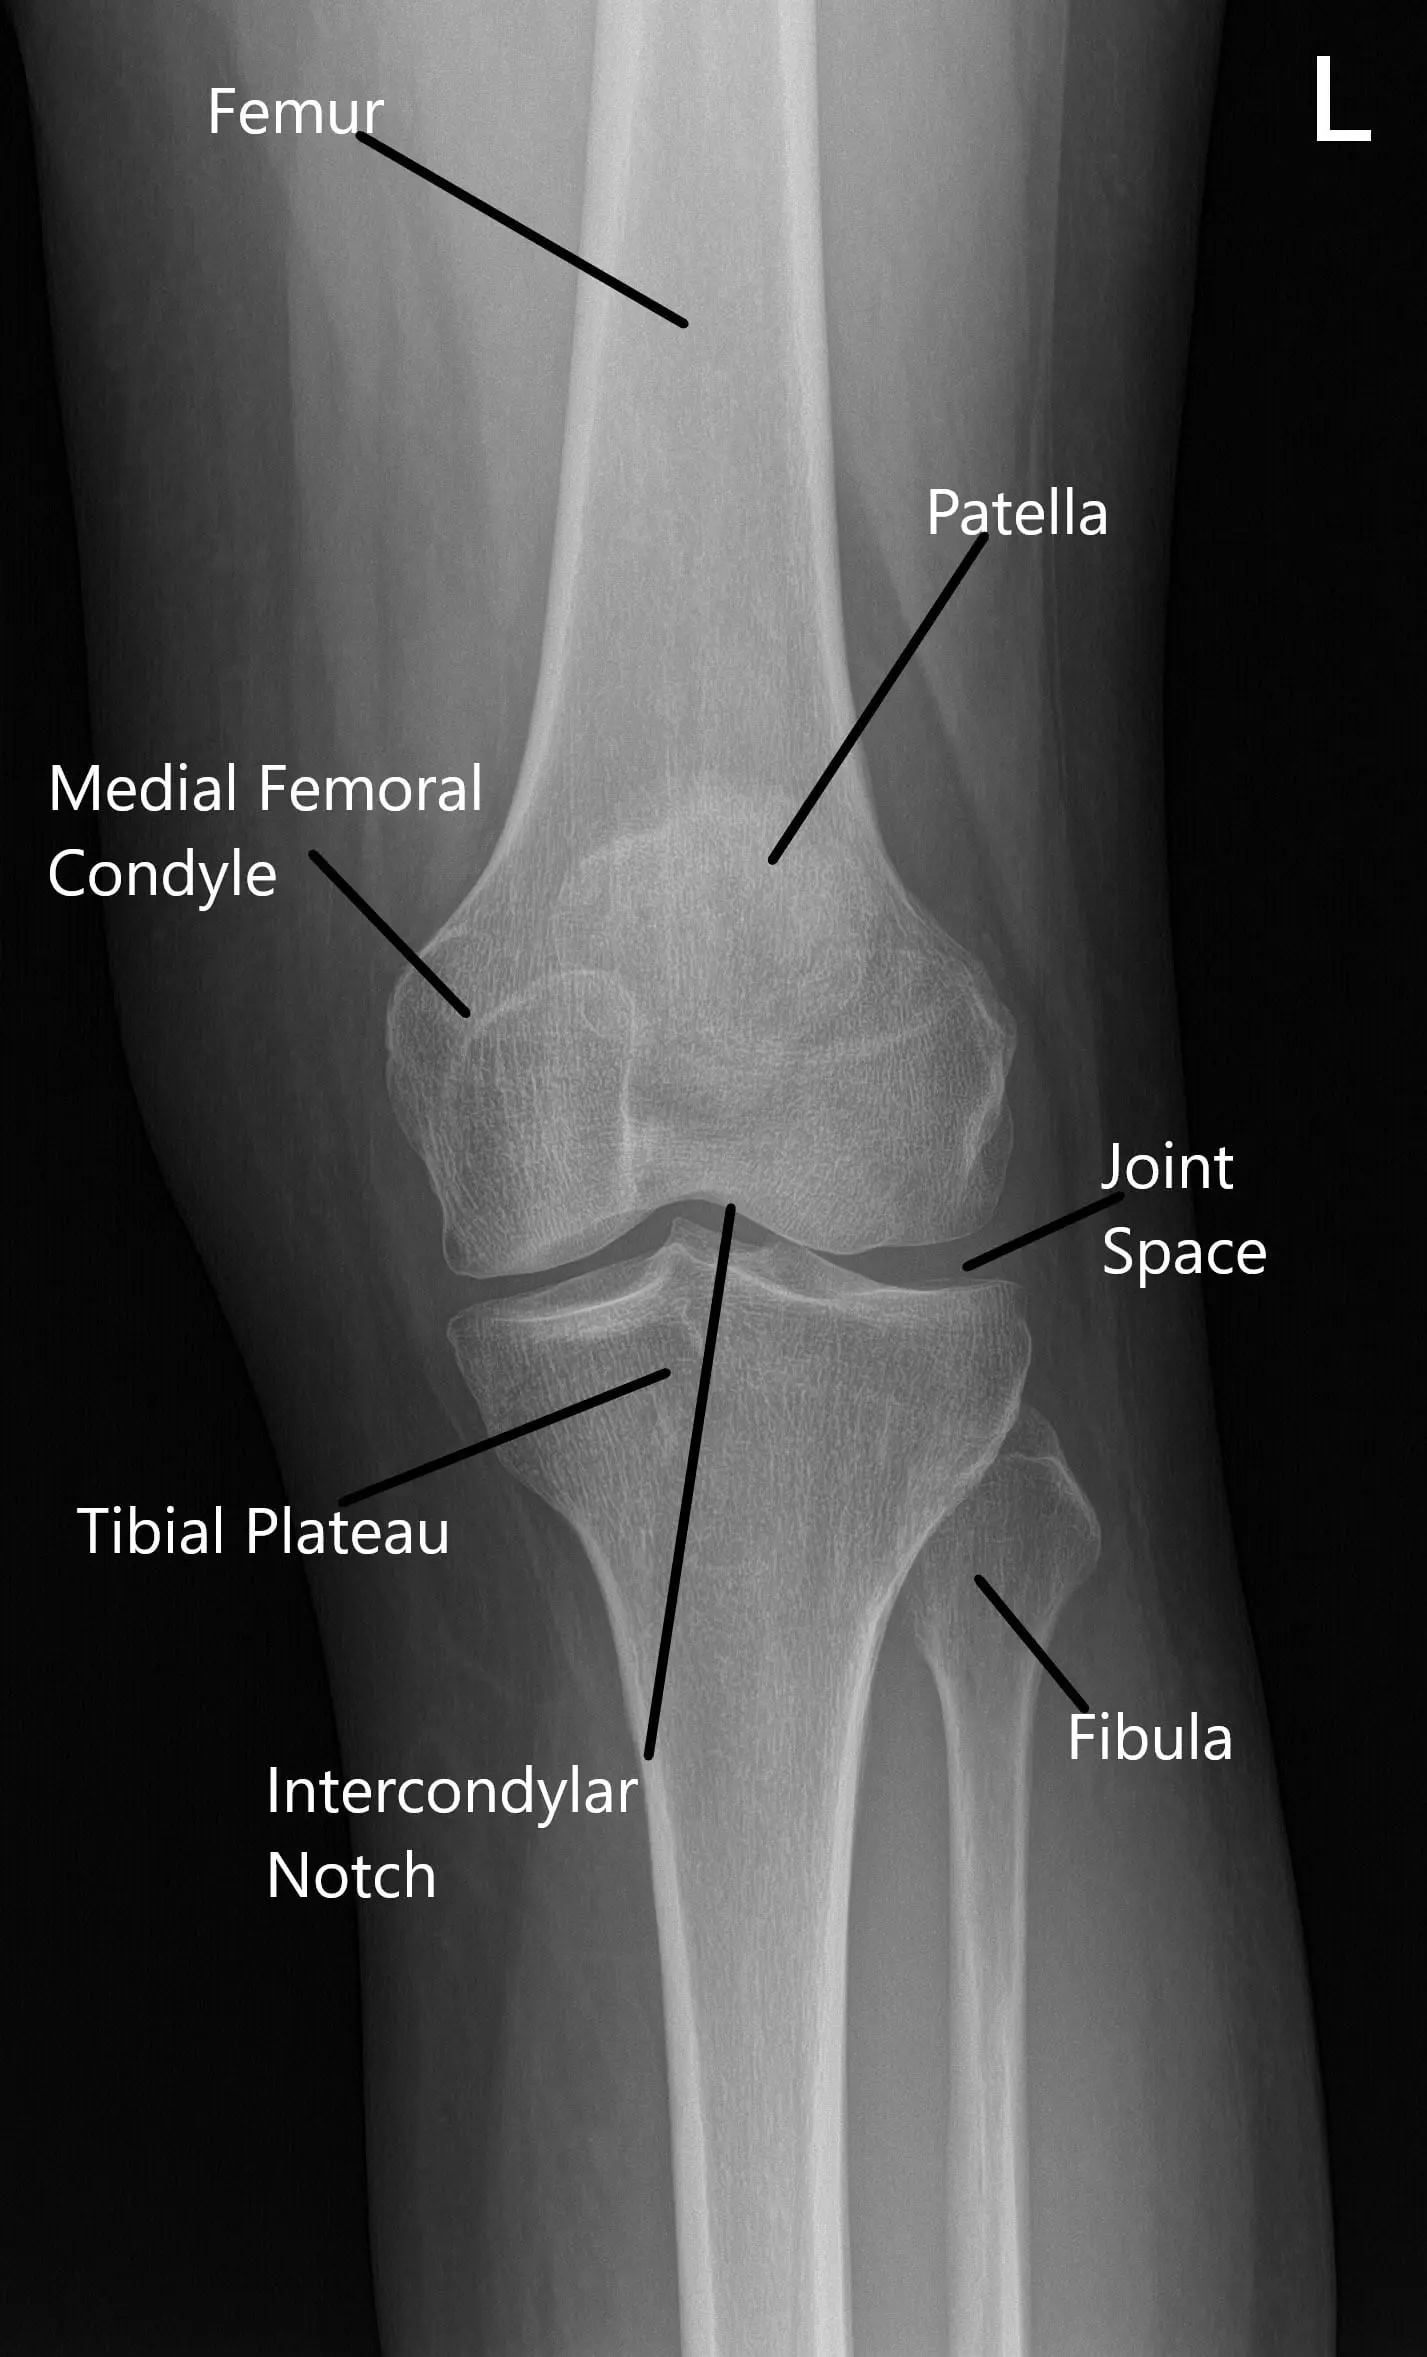

The patellofemoral joint is where the patella (kneecap) rests within the groove of the femur (thigh bone). The knee joint functions by allowing smooth bending and straightening movements, with the patella helping to stabilize and guide these motions. In PFPS, the alignment of the kneecap becomes compromised, often due to muscle imbalances, tight ligaments, or poor training, leading to pain and discomfort.

Normal X-ray of the knee joint showing the various structures in the Anteroposterior and Lateral view 2

Normal X-ray of the knee joint showing the various structures in the Anteroposterior and Lateral view.